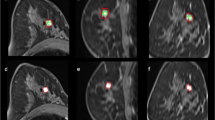

To investigate the diagnostic capability of whole-lesion (WL) histogram and texture analysis of dynamic contrast-enhanced (DCE) MRI inline-generated quantitative parametric maps using CAIPIRINHA-Dixon-TWIST-VIBE (CDTV) to differentiate malignant from benign breast lesions and breast cancer subtypes.

From February 2018 to November 2018, DCE MRI using CDTV was performed on 211 patients. The inline-generated parametric maps included Ktrans, kep, Ve, and IAUGC60. Histogram and texture features were extracted from the above parametric maps respectively based on a WL analysis. Student’s t tests, one-way ANOVAs, Mann-Whitney U tests, Jonckheere-Terpstra tests, and ROC curves were used for statistical analysis.

Compared with benign breast lesions, malignant breast lesions showed significantly higher Ktrans_median, 5th percentile, entropy, and diff-entropy, IAUGC60_median, 5th percentile, entropy, and diff-entropy, kep_mean, median, 5th percentile, entropy, and diff-entropy, and Ve_95th percentile, diff-variance, and contrast, and significantly lower kep_skewness and Ve_SD, entropy, diff-entropy, and skewness (all p ≤ 0.011). The combination of all the extracted parameters yielded an AUC of 0.85 (sensitivity 76%, specificity 86%). kep_contrast showed a significant difference among different subtypes of breast cancer (p = 0.006). kep_skewness showed a significant difference between lymph node–positive and lymph node–negative breast cancer (p = 0.007). The IAGC60_5th percentile had an AUC of 0.71 (sensitivity 50%, specificity 91%) for differentiating between high- and low-proliferation groups of breast cancer.

The WL histogram and texture analyses of CDTV-DCE-derived parameters may give additional information for further evaluation of breast cancer.